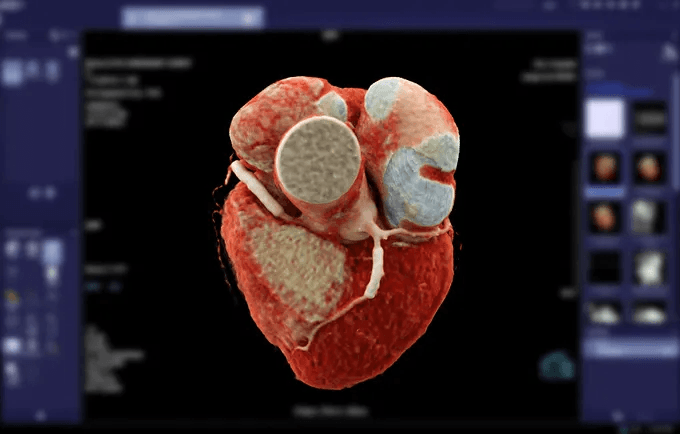

A Angiotomografia de coronárias é um exame diagnóstico não invasivo, de baixo risco, que utiliza contraste iodado e permite a perfeita visualização de placas de gordura ou cálcio no interior das artérias do coração e definir se estas estão causando obstruções.

É indicada nos casos de dor torácica (Doença Arterial Coronariana Crônica ou Síndrome Coronariana Aguda), avaliação de stents coronários, avaliação de patência de enxertos após cirurgia de revascularização miocárdica, seguimento de pacientes com Kawasaki. Também utilizada para planejamento de procedimentos de correções de doenças valvares.